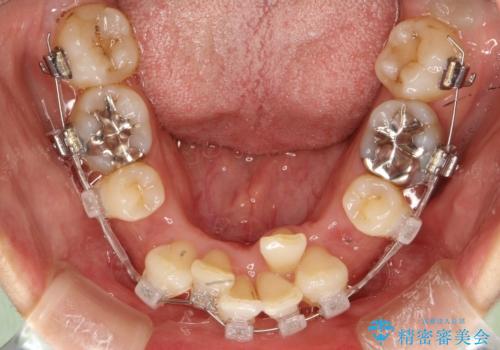

重度のガタガタと出っ歯をワイヤーによる抜歯矯正で整った歯並びへ

- 全体的ながたがたを主訴に来院されました。

上顎の前歯は前方に傾斜して、下顎の前歯は強いガタガタが見られました。

前から4番目の歯を上下左右合計2本抜歯して、歯並びを整える計画としました。

ワイヤー矯正にて治療しました。